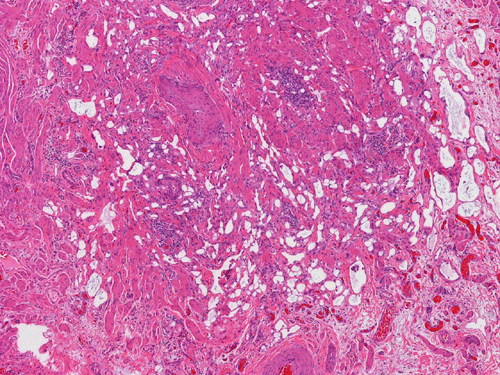

On scanning magnification, there is a round lesion in tissue around the fallopian tube (arrows in Panel A). The lesion does not invade into the tube nor distort or compress the tube. The cross sectional dimension is about the same diameter of the fallopian tube. On low and medium magnification, the lesion is composed of a collection of small microcysts intermingled with the smooth muscle bundles of the wall of the fallopian tube (Panel B and C). On higher magnification, the cyst or gland like spaces are lined by epithelioid to spindle cells with bland nuclei and an abundant amount of amphophilic cytoplasm (Panel D and E). The spindle cells are positive for calretinin, cytokeratin 5/6, and inhibin (Panel F, G, and H).

Histologically, the salient feature is small, microcystic or gland-like cystic spaces lined by flattened cells. Some of the tumor cells may arrange in cords and tubules.  Hyaluronic acid rich material that can be easily demonstrated by Alcian blue stain are present in the small glands and cysts. The tumor cells are medium in size and contain moderate to abundant amphophilic to eosinophilic cytoplasm. Prominent cytoplasmic vacuoles that suggest signet ring cells may be present. This is an important feature to know in order not to confuse these tumors with primary and metastatic carcinomas particularly when the specimen is obtained from the ovary. Although these tumor appears well-circumscribed on gross examination, these tumor appears infiltrative on microscopically and should not be confused with adenocarcinoma. The key to avoid this pitfall is that adenomatoid tumor have bland nuclear feature and no mitotic figures. Infaction can occur in adenomatoid tumor.